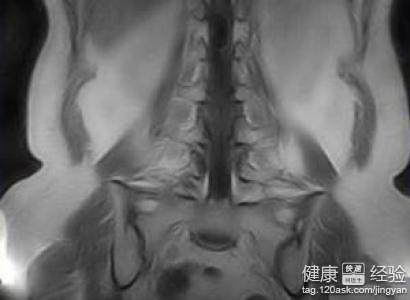

3患者要是發現自己有胸痛氣斷或者聲音沙啞的時候,要注意提醒自己去醫院進行檢查。醫生的建議是最好的治療方法通過檢查縱膈的情況進行CT檢查,縱膈腫瘤先發現後,要確認好明確氣管旁邊和隆突下有無腫大的淋巴結,這個很重要。

患者要注意,對有神經症狀及椎孔擴大的病例術前應行脊髓造影。在典型的良性神經鞘瘤的手術,手術切除也沒有什麼困難,但啞鈴狀神經鞘瘤手術需胸外與神經外科醫生共同完成。